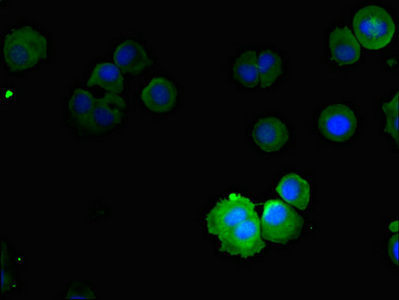

Immunofluorescent analysis of MCF-7 cells using CSB-PA138304ESR2HU at dilution of 1:100 and Alexa Fluor 488-congugated AffiniPure Goat Anti-Rabbit IgG(H+L)